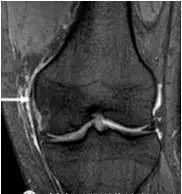

4、桶柄状撕裂

为纵形撕裂伴碎片向内侧移位,这种移位的片段类似于桶的柄,该型撕裂几乎累及半月板的所有部位,常易漏诊,在 MRI 上可以有多种表现,主要为半月板的宽度减小,在通过半月板体部的冠状面上未见到与对侧半月板共同构成的蝶形表现,同时可见到内移的半月板碎片位于髁间窝或交叉韧带旁,可形成双前、后交叉韧带征,这一征象在诊断半月板桶柄状撕裂中有重要意义;